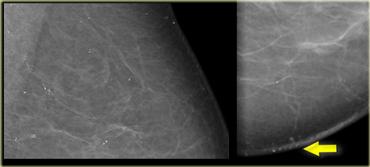

Bên trái là hình ảnh của một bệnh nhân với một vài vôi hóa thô không đồng nhất.

Chúng được phân loại là BIRADS 3 (có khả năng lành tính với xác suất ác tính dưới 3%).

Tại lần theo dõi sáu tháng, số lượng vôi hóa đã tăng lên và kết quả sinh thiết phát hiện DCIS.